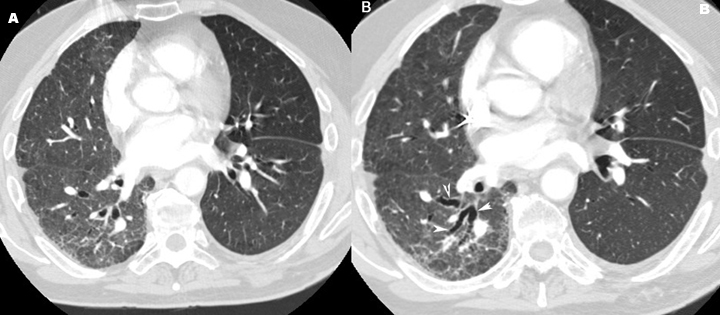

Bronchiectasis

• A: Note artery next to dilated bronchi (signet ring).

• B: Arrowheads point to bronchiectasis of lower lobe on right as dilated tubular shadows.